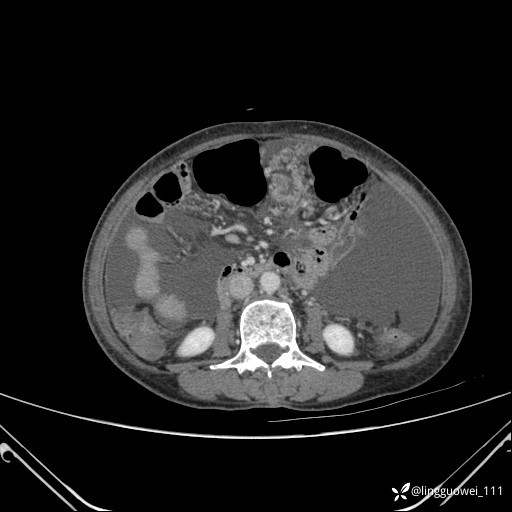

病例女,65岁,门诊行胃肠镜检查后,说腹胀入院检查,CT能发现病因吗?已公布结果

主诉:门诊行胃肠镜检查后,诉腹胀,入院检查,肝有病变吗?腹膜及腹腔的表现有特征性吗?

平扫: